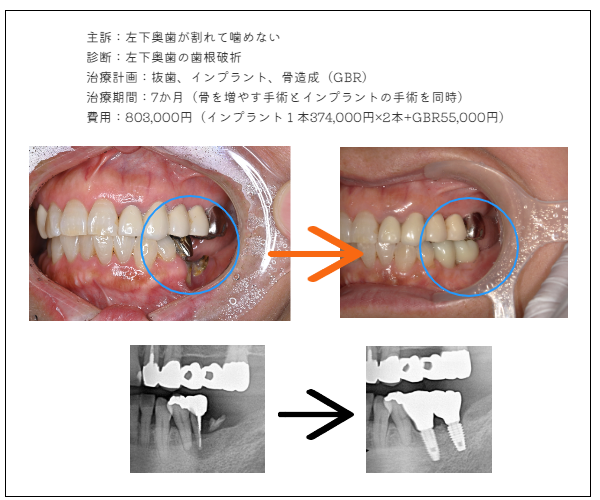

imprant症例3

MYデンタルインプラント